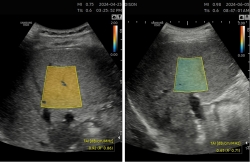

삼성메디슨(대표 유규태)이 삼성서울병원과 '티에이아이(TAI, Tissue Attenuation Imaging)' 등 지방간 정량화 초음파 솔루션을 건강검진에 활용한 결과가 담긴 백서를 발간했다.티에이아이는 초음파 신호가 간세포 내 지방에 의해 약해지는 정도를 측정해 실시간으로 지방간을 정량화하는 기술로, 지난 2022년 9월 한국보건의료연구원으로부터 신의료기술로 인정받았다.이번에 발간된 백서에는 삼성서울병원 건강의학본부 변영혜 교수팀이 지난 2년간 티에이아이를 사용하며 정립한 건강검진용 표준활용법 및 환자 관리 프로세스 관련 …